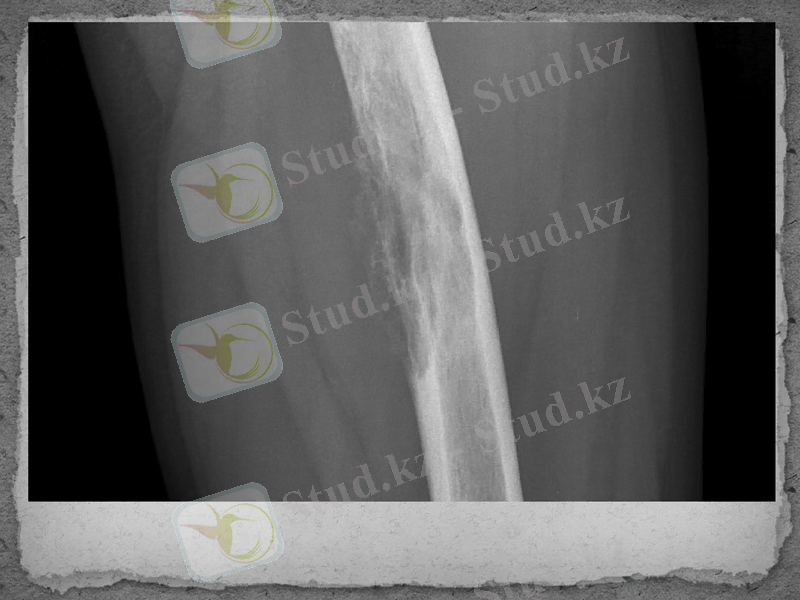

Остеомилиттiң созылмалы түрінде рентген аппараты арқылы тексергенде сүйек бетi қабаттарының қалындағанын (гиперостоз), сүйектiң кортикальды жағында, сүйек ұлпаларында қуыстары көбейедi (остеопороз) және өлi ұлпалары кездеседi. Сүйек айналасындағы жұмсақ ұлпалардың iсiгi аздау болып, қабынған сүйектiң пiшiнi жақсы көрiнедi.

Диагнозы. Рентгенография жасау арқылы қойылады.